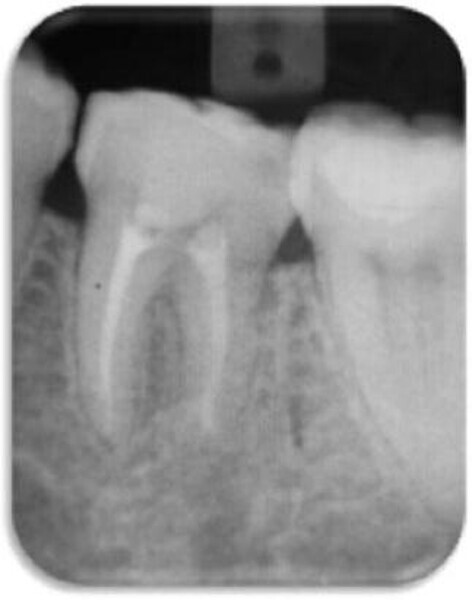

Leczenie endodontyczne autogennego przeszczepu zęba